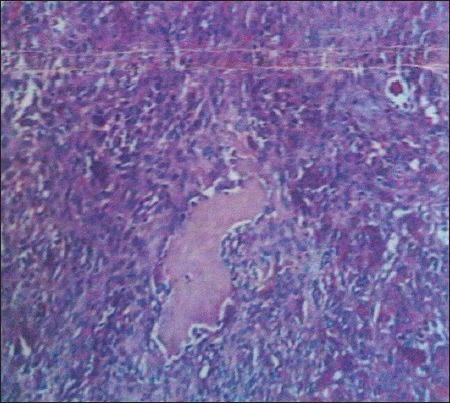

Giant cell tumor of the clivus with presence of epithelioid histiocytes.

Giant cell tumor (GCT) is a benign neoplasm but locally aggressive tumor that uncommonly involves the skull bone. We report a case of a 62-year-old male presented with increasing headache and diplopia. Investigations were suggestive of an expanding mass lesion of the clivus. Histopathology was suggestive of diagnosed with GCT with abundant histiocytes.